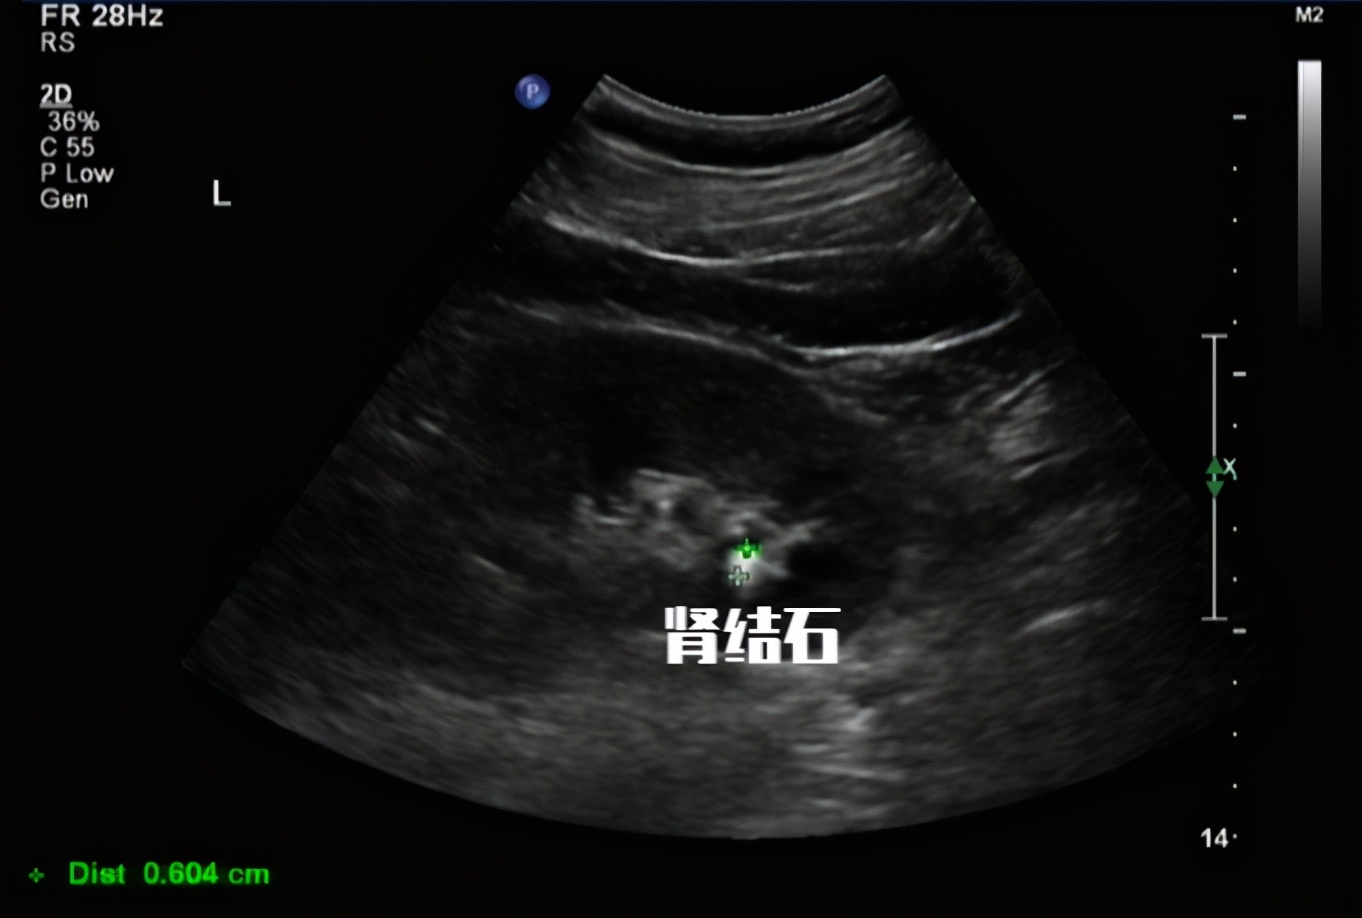

约14%的痛风患者曾有结石病史.而在2019年我国最新的一项单中心研究中显示,有高达50%的痛风患者经超声筛查均存在结石或既往曾有结石病史.